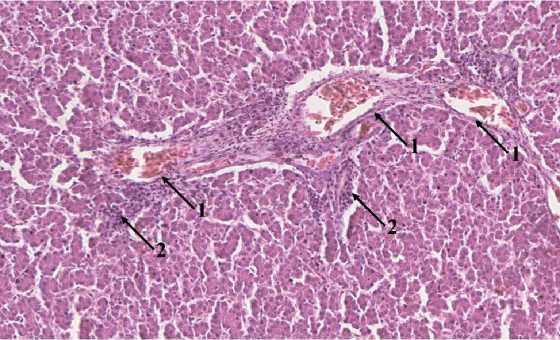

При гистологическом исследовании структура паренхимы печени цыплят-бройлеров всех групп в возрасте 1-х суток имела гомогенный незрелый вид, печеночные балки были неразличимы, синусоиды различались с трудом. Цитопл-зама гепатоцитов была тотально заполнена оптически прозрачными везикулами, ядра были округлыми, везикулярными с мелкодисперсным хроматином. Центральные вены и портальные тракты определялись отчетливо, вокруг последних отмечался умеренный периваскулярный отек (рис. 1).

Рисунок 1 — Паренхима печени 1-суточного цыпленка-бройлера перед разделением на группы: 1 - центральная вена; 2 - ветвь портальной вены в составе портального такта Гематоксилин+эозин, х100.